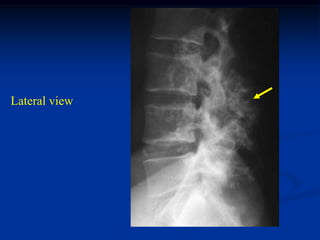

38 year male

osteochondroma

L-5

Lateral view